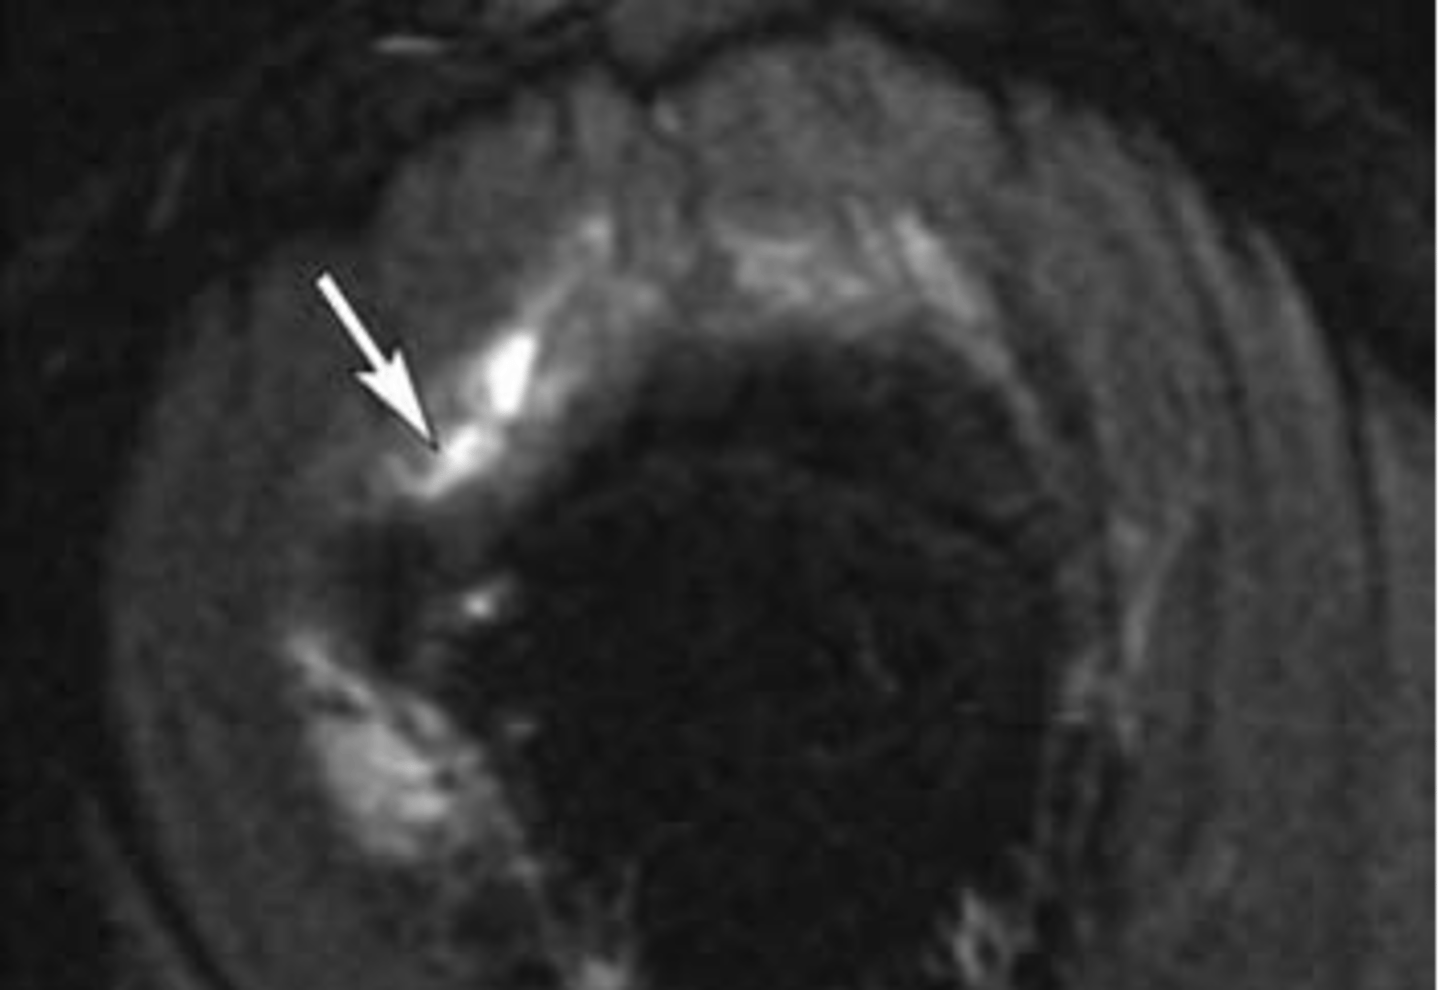

Partial rotator cuff tear -- focal area of disruption

What is this image depicting w/ the rotator cuff? How do you know?

Full thickness rotator cuff tear -- 100% of the fibers are involved